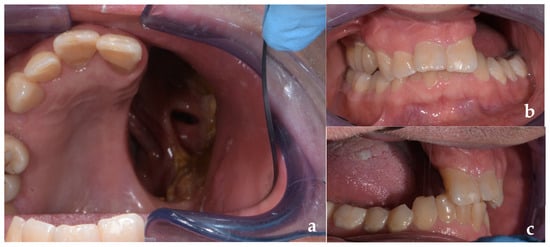

2. Clinical Case Presentation

2.1. Surgical Procedures

2.2. Prosthetic Management